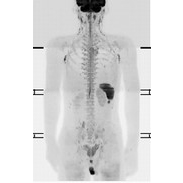

核医学検査

特定の臓器や組織に集まりやすい性質を持った放射性医薬品を体内に投与し、そこから放出される放射線をガンマカメラで画像化することにより体内の様子を調べる検査です。

CTやMRIは、主に臓器の形態の異常を調べるのに対し、核医学検査は、投与された放射性医薬品の分布や集積量、経時的変化の情報から、臓器や組織の形態だけでなく、機能や代謝状態などを評価することができます。

機能や代謝状態の異常は形態変化の前に発現しますので、核医学検査によって病変の早期発見につながる可能性があります。

当院では全身骨、脳、心臓など、多くの部位の検査を行っています。